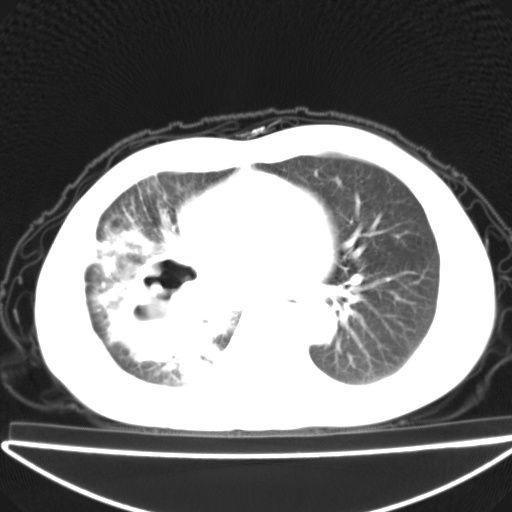

以下是引用jsgdoctor在2008-11-6 22:12:00的发言:[br]右主支气管壁明显增厚,管腔狭窄.考虑为右侧中央型肺癌伴阻塞性炎症\\肺脓肿.

以下是引用zjzjr在2008-11-6 20:25:00的发言:[br]中心型肺ca,合并阻塞性肺炎

以下是引用zsl6918在2008-11-6 19:43:00的发言:[br]右侧中心性肺癌(鳞癌)